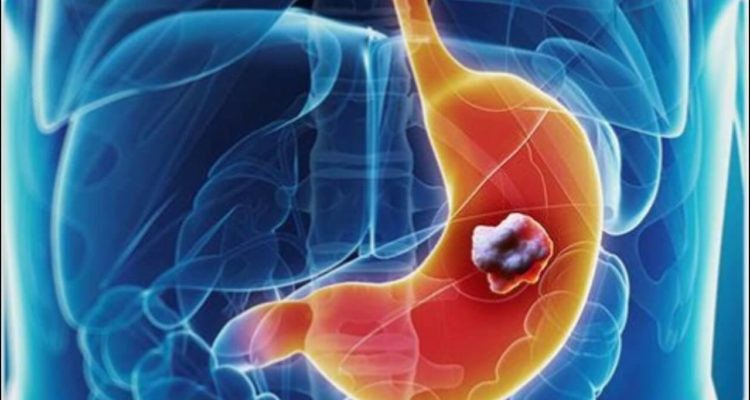

Шлунок – незамінний орган: саме сюди потрапляють усі продукти та напої, що вживаються за день. Потім їжа переробляється за допомогою шлункового соку та транспортується невеликими порціями в тонку кишку. Рак шлунка (карцинома) часто не розпізнається до пізньої стадії, тому що перші симптоми не завжди очевидні.

«Симптоми, пов’язані з раком шлунка, є досить неспецифічними. Першими проявами захворювання можуть бути проблеми із травленням, нудота, втрата апетиту, дискомфорт у животі», – наголошують лікарі.

З розвитком пухлини можуть виникати інші симптоми. Наступні ознаки вимагають оперативного звернення до лікаря.